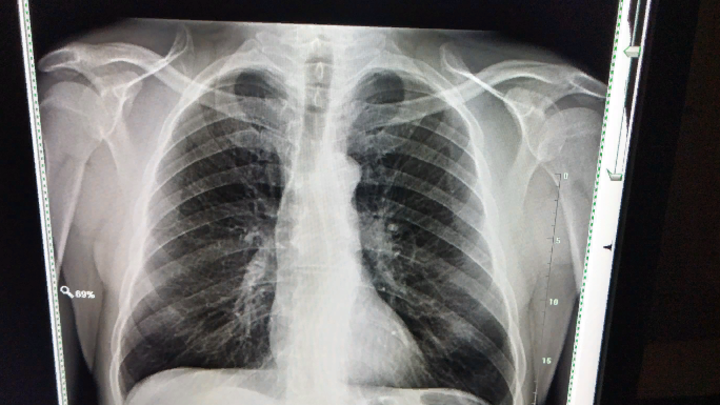

Рентгеновский снимок раскрыл причину постоянного кашля

На протяжении долгого времени британец страдал от кашля. Раскрыть неожиданную причину такого состояния помог рентгеновский снимок.

В бразильском Ботукату мужчина обратился в больницу с жалобой на постоянный кашель. Ничего не подозревающие врачи направили местного жителя на рентген, однако снимок показал десятки остатков личинок ленточного червя. По информации Daily Mail, все они выглядели как яркие пятна, но уже позже медики поняли, о чём идёт речь.

Уточняется, что такое состояние называется цистицеркозом. Возникает оно при попадании личинок свиного цепня, обитающего в кишечнике, в мышцы или мозг. Уже в человеческих тканях они создают некие твёрдые узелки, которые похожи на кисты и даже ощущаются под кожей как небольшие шишечки.

Кроме того, цистицеркоз может развиваться при проглатывании яиц ленточных червей. Чаще всего они обитают в непрожаренной свинине, воде или других продуктах, поэтому важно следить за их качеством.

Несмотря на то, что изначально такое состояние безвредно для людей, оно всё же может приводить к тяжёлым последствиям. Например, при попадании личинок в мозг возникают судороги или скопление жидкости в органе, что приводит к летальному исходу. При этом именно цисты личинок Taenia solium являются причиной до 70 процентов случаев эпилепсии в мире.